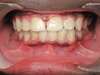

Avant / Après